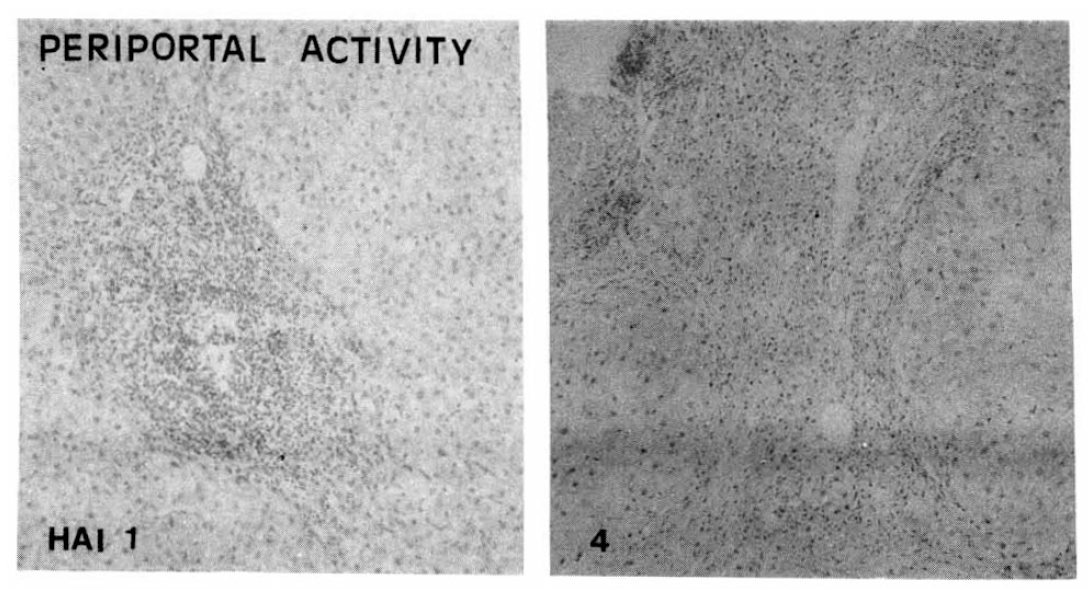

1. Portal Inflammation

The follicular portal inflammation with dense lymphocytic infiltrates was noted in ten cases of the CAH-C group (52.6%), whereas only in five cases of the CAH-B group (25.3%). There were statistically significant differences in the morphologic changes of portal inflammation between these two groups (Table 3, Fig. 1).

5. Sinusoidal Lymphocytic Reaction

More severe sinusoidal lymphocytic reactions in relation to the degree of the hepatic necrosis were noted more frequently in the CAH-C group (57.9%) than in the CAH-B group (31.6%). Thus, severe sinusoidal lymphocytic reaction can predict the morphologic characteristics of CAH-C (Table 8, Fig. 6).

Sinusoidal Lymphocytic Reaction

Fig. 6.

Histopathologic appearance of sinusoidal lymphocytic reaction, mild to moderate (HAI 1, left) and severe sinusoidal lymphocytic reaction (HAI 2, right).

From the above findings, the follicular and severe portal inflammation with prominent sinusoidal lymphocytic reactions were more prominent findings in chronic hepatitis C rather than chronic hepatitis B (Table 12, Fig. 9)

Fig. 9.

The follicular and severe portal inflammations (above fig.) with sinusoidal lymphocytic infiltrations (below fig.) were more prominent findings in chronic hepatitis C than chronic hepatitis B.